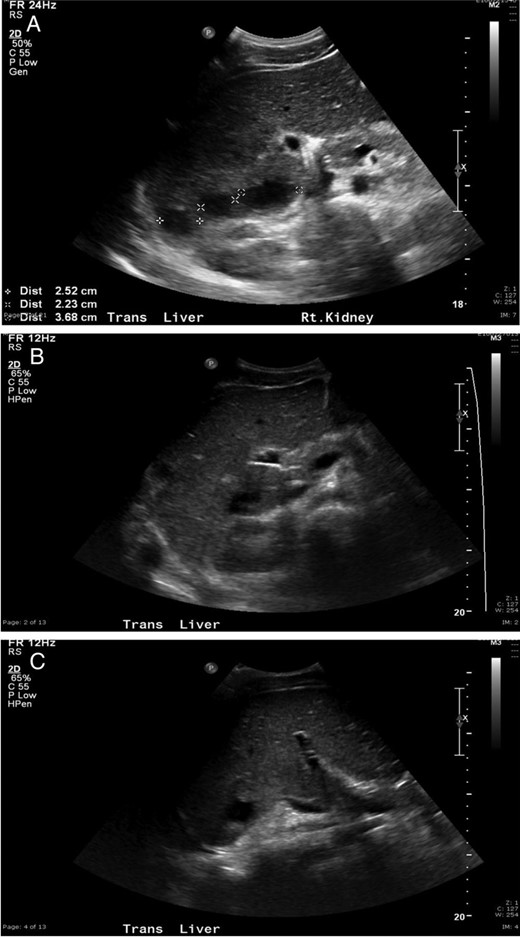

An 18-year-old, previously healthy college student presented to our hospital with a chief complaint of abdominal pain. He also reported 4 days of high-grade fevers, nausea and emesis. A computed tomography scan of the abdomen with IV contrast at an outside institution showed multiple hepatic abscesses (Fig. 1). Aside from several days of upper respiratory symptoms and odynophagia, a review of systems was negative. He denied any alcohol, illicit drug or tobacco use. On initial examination, the patient was tachycardic, normotensive and febrile to 39.2°C. Aside from minimal right upper quadrant tenderness, the remainder of the physical examination was normal. He had no dental disease. Laboratory data showed leukocytosis of 25 000/µl, erythrocyte sedimentation rate (ESR) 66, International Normalized Ratio 1.41, aspartate transaminase 32, alanine transaminase 50, alkaline phosphatase 147 and direct bilirubin 0.5. A transthoracic echocardiogram showed no valvular lesions.

Multiple lucencies noted within the liver consistent with abscesses along with a thickened gallbladder.